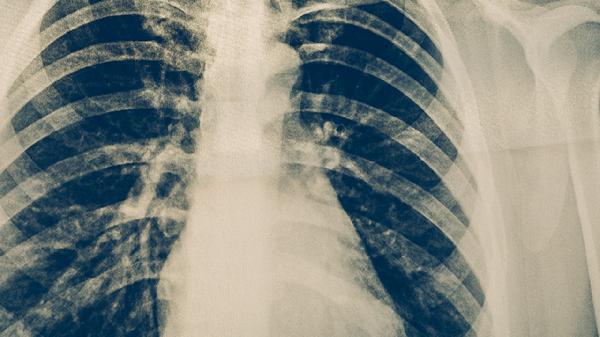

二、进行胸部影像学检查

胸部X线或CT检查是诊断肺炎的重要依据。支原体肺炎的影像学表现多样,典型特征包括肺部出现斑片状、云絮状的模糊阴影,密度较淡,边缘不清,多分布于肺下叶。部分患者可表现为间质性肺炎的改变,如肺纹理增粗、紊乱,或出现网格状、结节状阴影。影像学检查可以明确肺部炎症的范围和性质,但同样不能直接确定病原体为肺炎支原体,需要与其他类型的肺炎相鉴别。